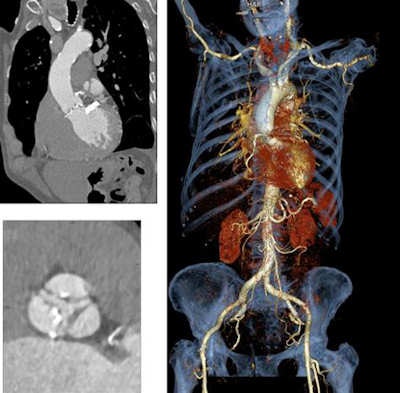

Traditionally, TAVI planning with CT has required two separate scans, one focusing on the heart and a second scan of the thorax in order to image the access vessel for the TAVI procedure. But a dual-source CT technique was recently developed to capture all of the relevant anatomy in a single scan.

"We derive the vessel diameters from the dataset and determine the angulation so we can determine the implantation later on," he said. "The workstation also helps us very much to display the access route and the course of the aortic arteries and [determine] whether the catheter and sheath can be pushed through the iliac arteries to perform the procedure at all."

The image quality of high-pitch, whole-body CT angiography with single-source CT was not significantly different from dual-source CT, Becker said, and no significant differences were seen in evaluability, image noise, or signal intensity. Radiation exposure was slightly lower for single-source CT (3.3 ± 0.7 mSv) versus DSCT (4.3 ± 0.8 mSv), and single-source CT also had the advantage of more homogeneous enhancement of vasculature.